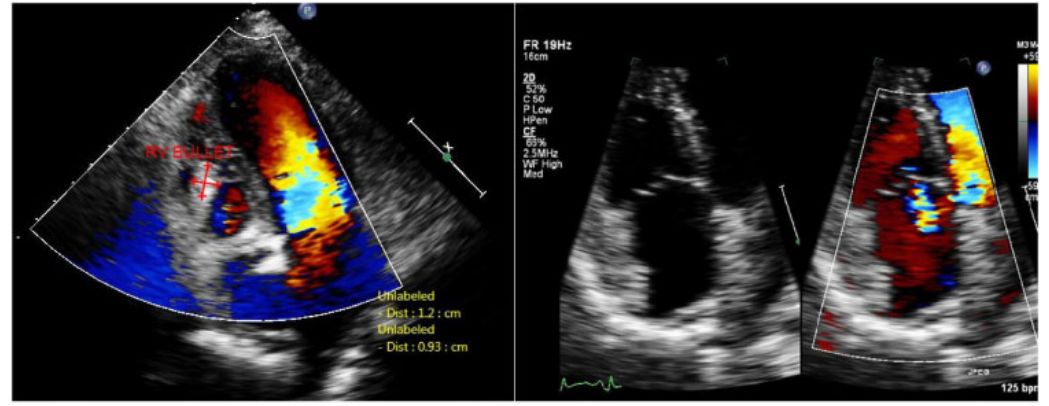

经胸超声心动图(TTE)后角心尖四腔观显示*弹子**位于右心腔内,如图2左。四腔观显示,轻度三尖瓣反流,室间隔完整,无心包积液,如图2右图。

图2 左:后角心尖四腔观显示*弹子**位于右心腔内;右:四腔观显示轻度三尖瓣反流。

注:在常规四腔视图中,未发现*弹子**在右心室。